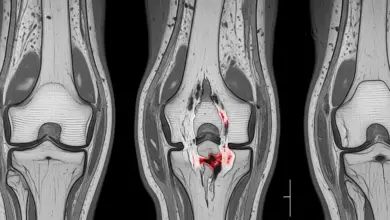

A osteotomia no joelho valgo é uma cirurgia de realinhamento indicada em casos específicos, quando o desvio do eixo do membro passa a concentrar carga em excesso na parte lateral do joelho e começa a gerar dor, limitação funcional e desgaste progressivo.

No joelho valgo sintomático, a meta é redistribuir a carga que está passando de maneira exagerada pela região lateral do joelho.

A cirurgia é considerada quando existe relação clara entre desalinhamento, dor e sobrecarga no compartimento lateral do joelho.

O planejamento da osteotomia exige análise detalhada. Não basta confirmar que o joelho tem desvio. É necessário entender onde nasce a deformidade e quanto ela participa do quadro doloroso.

- Estado da cartilagem articular.